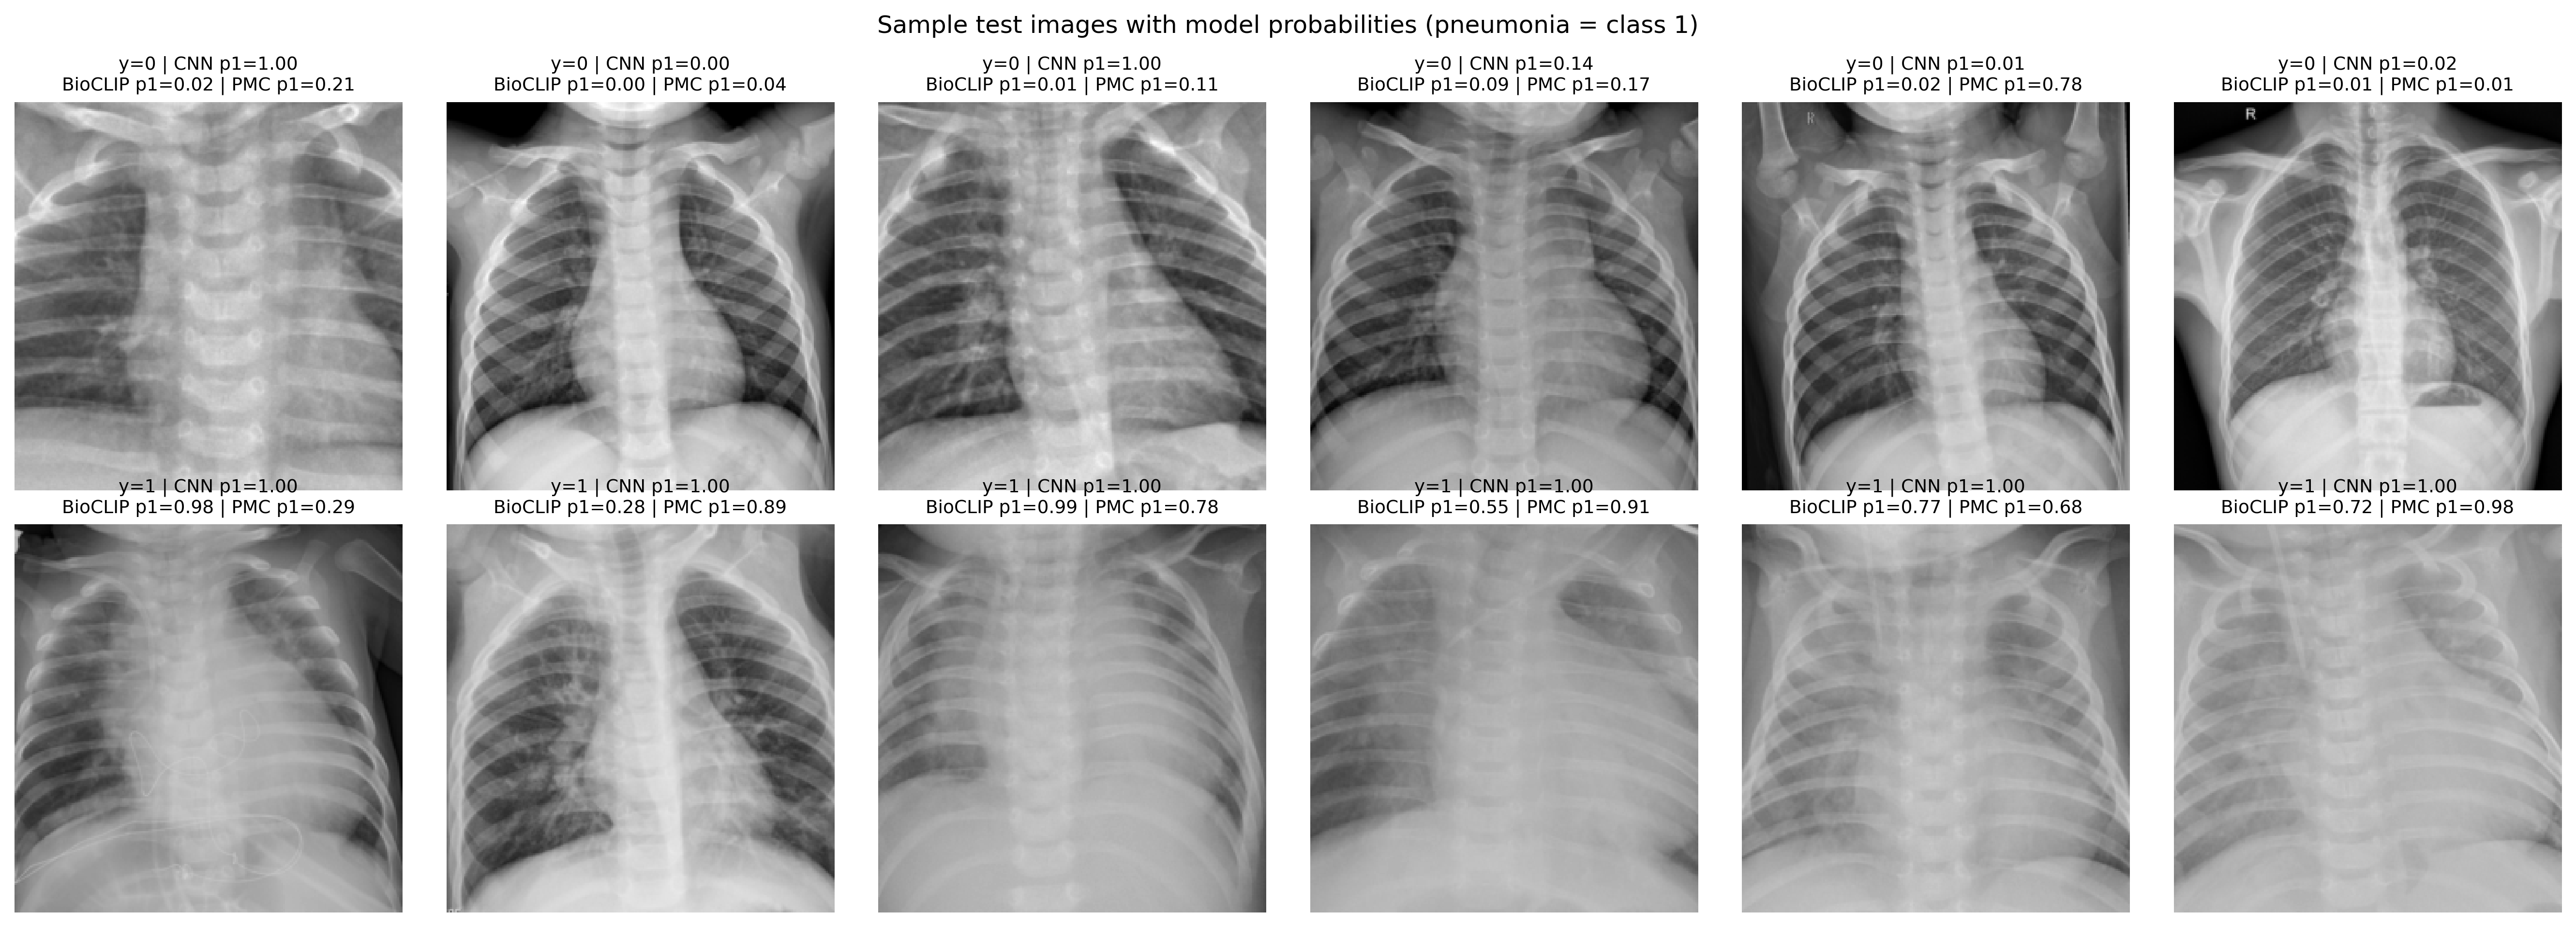

IV-D Qualitative Analysis

To better understand the models’ behaviors, we conduct a qualitative analysis of their predictions.

Figure 1 displays sample images from the PneumoniaMNIST test set. The trained CNN is highly confident in its predictions, with probabilities typically being either 1.00 or 0.00. In contrast, the zero-shot VLM provides more graded probabilities, which helps explain why threshold calibration is so impactful. Figure 2 shows a similar panel for the Shenzhen TB dataset, again illustrating the different probability distributions of the CNN and BiomedCLIP.